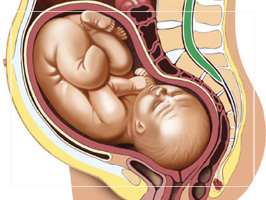

Gravidanza e parto / di - 29 Aprile 2010

Niente fumo ma taglio cesareo: ritratto della mamma italiana tipo

Fumano meno, prendono acido folico e seguono i corsi pre-parto. Ma resta ancora alto e addirittura in lieve aumento il numero di tagli cesarei nel nostro Paese e quello delle…